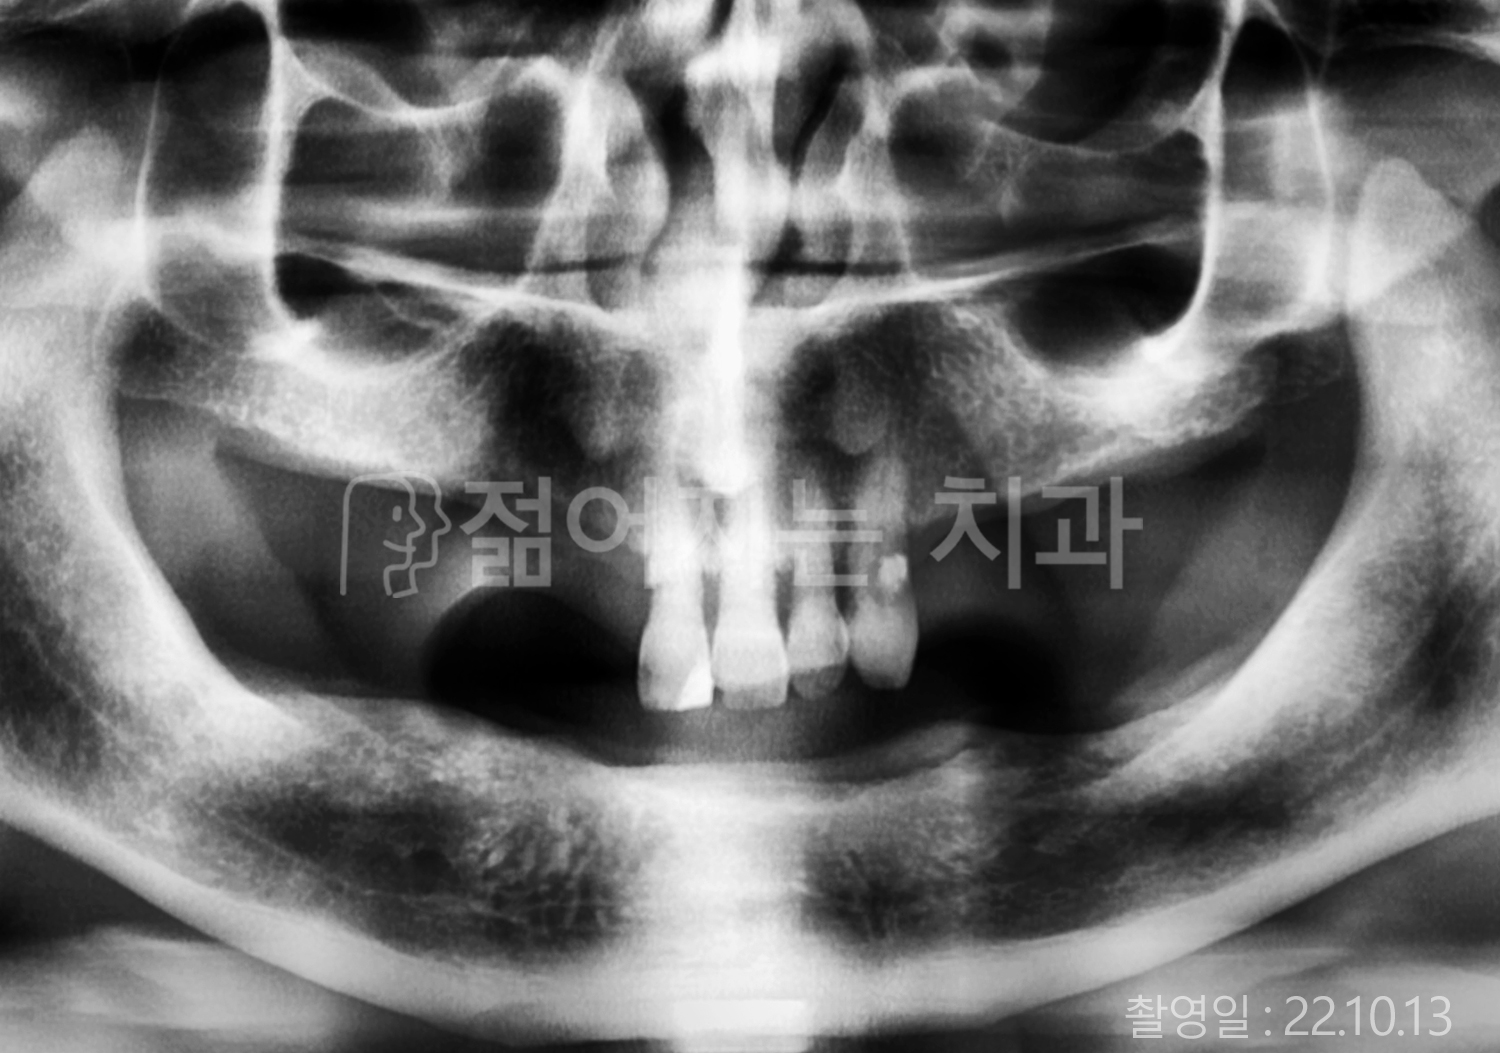

• 70대 고혈압, 고지혈증 전체치아 10개 이상 임플란트

• 60대 당뇨, 간염 전체치아 10개 이상 임플란트

• 80대 골다골증 전체치아 6개 이상 임플란트

• 70대 고혈압, 당뇨 전체치아 10개 이상 임플란트

• 60대 간 질환 전체치아 10개 이상 임플란트

• 60대 전체치아 10개 이상 임플란트

• 70대 전체치아 10개 이상 임플란트

• 50대 전체치아 10개 이상 임플란트

• 60대 고혈압, 고지혈증 전체치아 10개 이상 임플란트

• 40대 고지혈증, 뇌혈관 질환 전체치아 10개 이상 임플란트